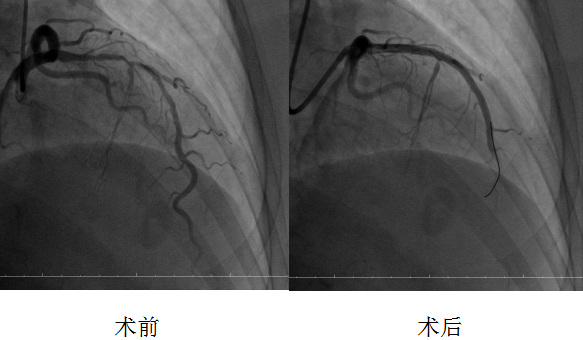

10月17日,在介入科的全力配合下,劉波主任主導(dǎo)開(kāi)展手術(shù)。手術(shù)團(tuán)隊(duì)運(yùn)用直徑僅1.5毫米的高速旋磨頭,以每分鐘15萬(wàn)轉(zhuǎn)的轉(zhuǎn)速精準(zhǔn)“打磨”血管內(nèi)鈣化病灶,三次旋磨成功打通病變通路,隨后順利為患者串聯(lián)植入兩枚藥物支架并以球囊行后擴(kuò)張。為確保手術(shù)效果,團(tuán)隊(duì)還通過(guò)血管內(nèi)超聲檢查精準(zhǔn)評(píng)估支架貼壁情況,對(duì)支架近端進(jìn)行補(bǔ)充后擴(kuò)張。復(fù)查造影顯示,支架釋放滿意,血管狹窄解除,血流恢復(fù)正常。術(shù)后1小時(shí)即實(shí)施雙泵透析,有效降低造影劑對(duì)腎臟的影響,保障了患者心腎功能穩(wěn)定。經(jīng)過(guò)后續(xù)規(guī)范治療,患者恢復(fù)良好,現(xiàn)已順利出院。